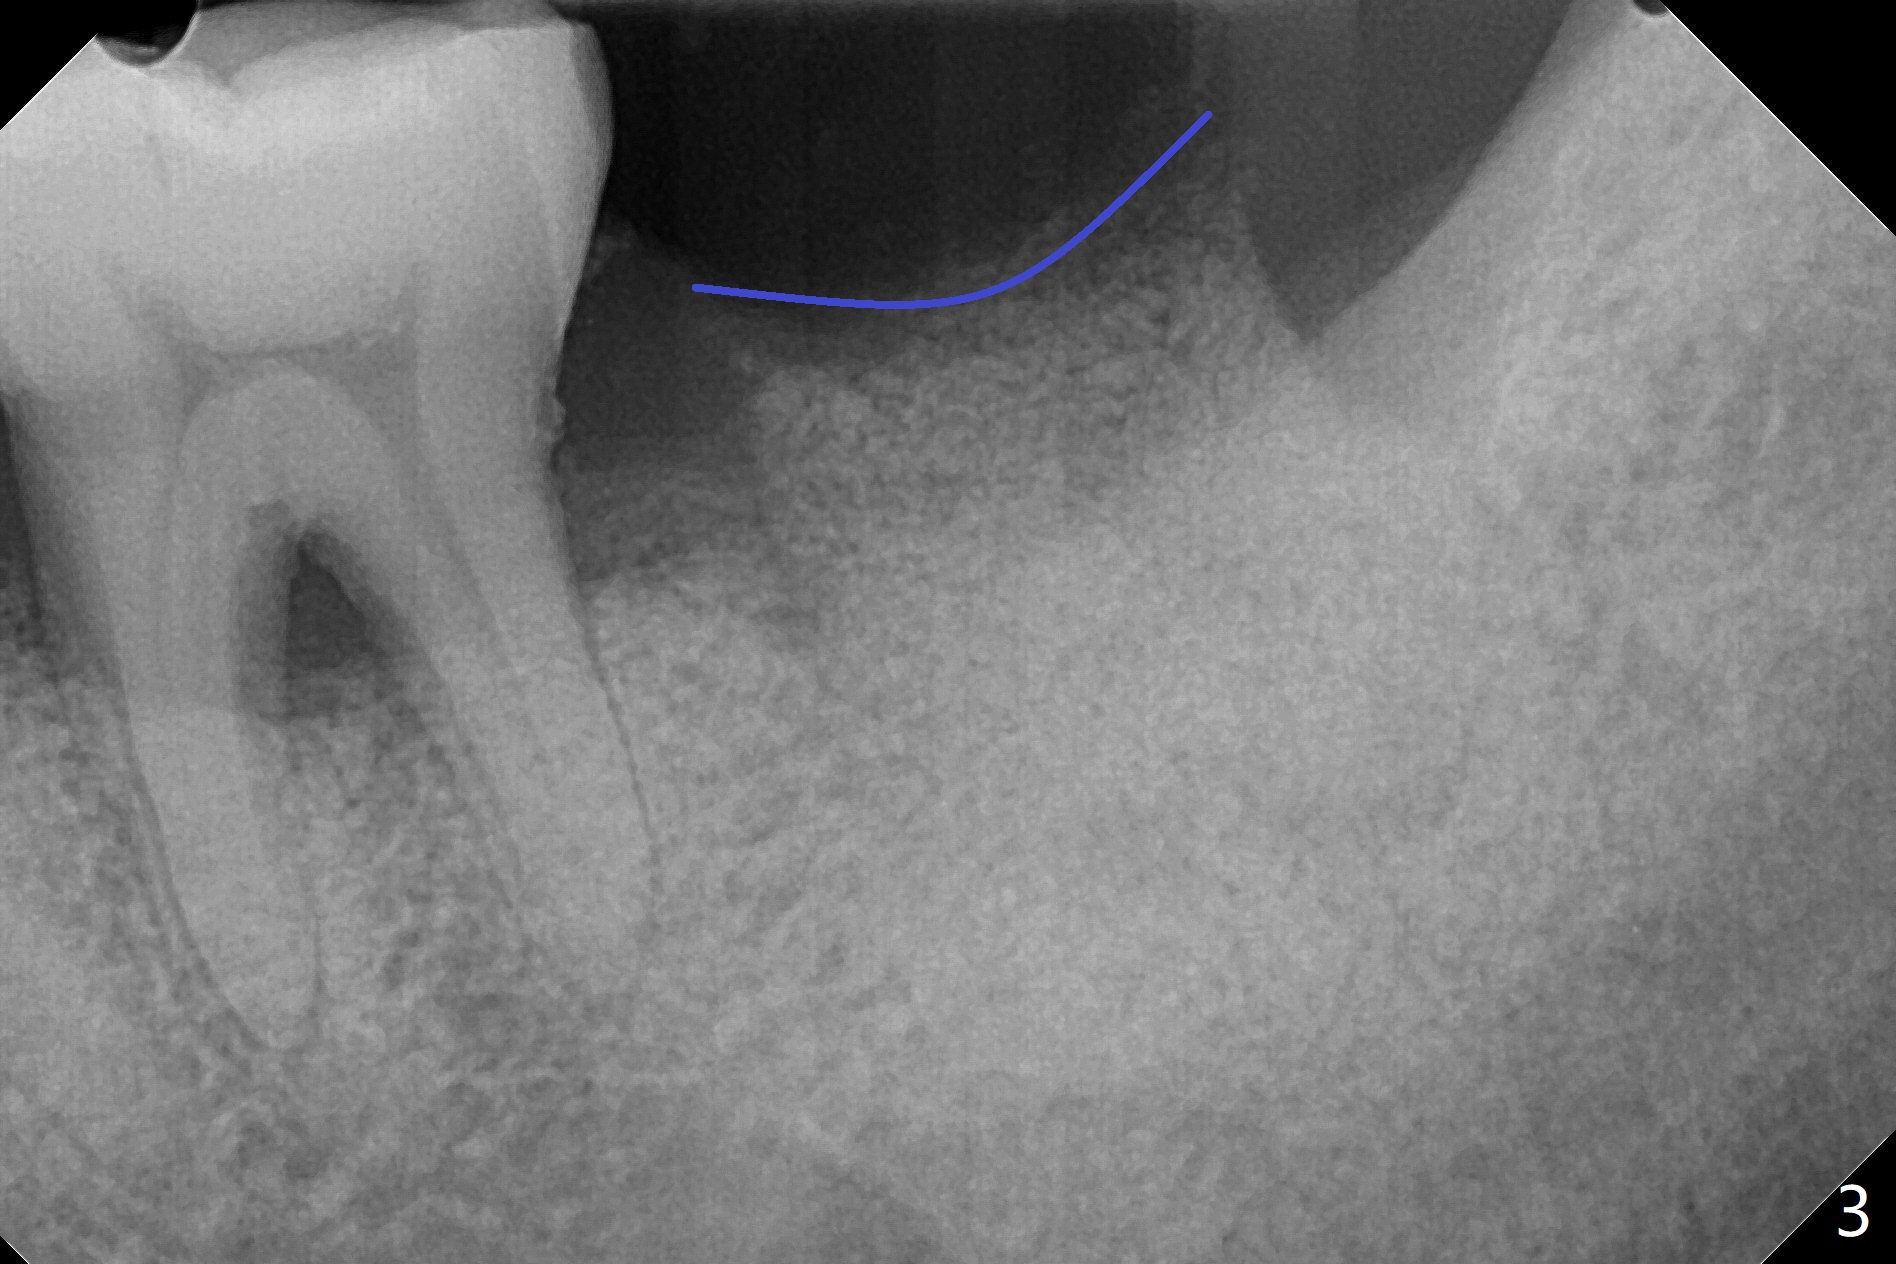

A 55-year-old man presents to clinic with nocturnal pain associated with the tooth #18 (Fig.1). After extraction and removal of granulation tissue, mineralized cortical allograft (particle size: 125μm – 850μm)) hydrated with .5 ml of .3 mg/ml of rhPDGF-BB (one component of GEM21S) is placed in the sockets with a thin septum (Fig.2 *). Periodontal glue is applied to the top layer of the bone graft (Fig.3 blue curved line). It appears that the bone graft becomes less mobile. GEM Cap RCM (regenerative collagen membrane, 9-12 month resorption time) is placed with the glue applied to the periphery of the cap, which seems to be quite stable (Fig.4). No suture is needed.